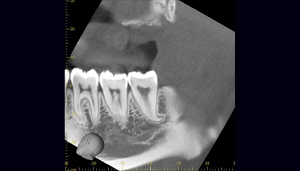

- 抜歯前写真(レントゲン)

- 抜去歯の写真(CT画像)

| 年齢 | 30代・女性 |

|---|---|

| 主訴 | 右下親知らずが疼く |

| 親知らずの生え方 | 横向きに生えている |

| 抜歯時間 | 40分 |

| 費用 | 約8,000円(保険診療、CT代含む) |

| 抜歯内容 | 右下の親知らずは横向きに生えて埋まっているため、麻酔をし親知らずの奥に切開を入れて歯ぐきを開き、歯を囲んでいる骨を削り歯の頭部分を割って出してから、残った根の部分を取り出して抜歯は終了しました。 歯ぐきを切った部分は糸で縫っています。このケースでは根の先端が神経に近く麻痺のリスクがありましたが事前にCTを撮影し、神経との位置関係を確認していたため、麻痺が残ることはありませんでした。 約1週間後に糸取りを行い、その際も多少の痛みや腫れはありましたが後日その痛みも無くなりました。 |